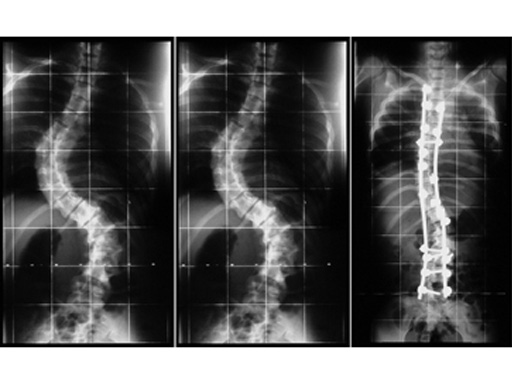

16-year-old woman with progressive kyphoscoliosis (scoliotic double curve: preoperative thoracic 78 and lumbar 68; postoperative 38 and 30); posterior instrumentation with pedicle screws in L1 to L5 and pedicle, lamina and transverse process hooks in T2 to T10 after anterior release.